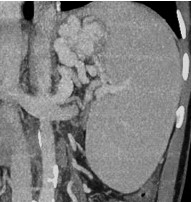

Hình 1: (A) Các vòng nối cửa chủ; (B) giãn TĨNH MẠCH phình vị trên nội soi và (C) trên MSCT